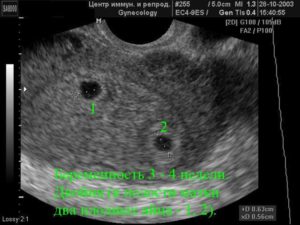

- уже на сроке 6 недель видно произошло одноплодное или многоплодное зачатие, и счастливые родители смогут готовиться к появлению близнецов или даже тройни;

Что касается многоплодной беременности и сроков, когда ее видно на УЗИ, временной интервал в этом случае не меняется — беременность видна все на том же сроке в 6 недель (от первого дня последней менструации).